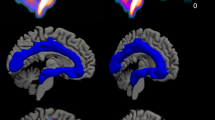

Parametric images were generated using the 3D stationary wavelet aided parametric imaging (WAPI) procedure, where the non-invasive Logan plot, fitted with multilinear regression, is applied on TACs from individual voxels43,44. For visualizations, the parametric images were registered to MNI-space45 and averaged across individuals.

ROIs preferentially sampling the dorsal- and median raphe respectively were created using a version of a previously described semi-automatic method44,49, here fully automated (Fig. 2, see Supplement 1 for details). For each individual, the resulting masks were applied to the WAPI-images to calculate a BPND value.

(1) FreeSurfer Brainstem Substructures. (2) The pons mask (green) was trimmed, keeping the most dorsal 5 voxels. (3) The resulting mask was overlaid on the time-weighted summated PET-image. (4) Median raphe is the structure with highest [11C]MADAM binding within the boundaries of the trimmed pons mask; the most intense PET-voxel was located and in an iterative process the voxel with highest intensity adjacent to the initial voxel was added until 65 voxels were collected. (5) The resulting mask overlaid on the MR-image. The same procedure was used to delineate a region preferentially sampling dorsal raphe except for using the midbrain mask (yellow in panel 1) and 116 voxels.

In A MADRS-S measurements during the course of ICBT. Each cell represents one patient, (n = 17), letters in lower left corner corresponds to the letters in Fig. 1, numbers in parenthesis is CGI-I. In B longitudinal [11C]MADAM data (n = 16) for the composite region, PET1 (baseline) and PET2 (after treatment). Right panel shows difference scores between scans. In C mean parametric image of patients at baseline (upper image) and after treatment (lower image; n = 16), see Supplement 3 for a 3D movie of the same data. In D longitudinal data, median raphe, BPND at PET1 (baseline, left) and PET2 (after treatment, right). In E cross-sectional data, median raphe, BPND for patients with MDD at baseline (left) and healthy controls (right). In F cross-sectional [11C]MADAM data (n = 17 + 17) for the composite region, comparing patients with MDD at baseline to matched healthy controls. Right panel shows difference scores between matched pairs.

BPND increased on average 10% in the composite region following ICBT; PET 1 Mean Z-score = −0.22 ± 0.68, PET2 Mean Z-score = 0.28 ± 0.89, t(15) = −3.01, p = 0.01, 95% CI [−0.85, −0.15], Dz = 0.75. Binding in median raphe showed no change following treatment; PET 1 Mean BPND = 2.81 ± 0.48, PET2 Mean BPND = 2.89 ± 0.53, t(15) = −0.67, p = 0.51, 95% CI [−0.31, 0.16], Dz = 0.17 (Fig. 3B–D, Supplement 3 for a 3D movie).

There was no evident difference in BPND between patients at baseline and healthy controls. [11C]MADAM binding in the composite region was on average 4% lower in controls compared to patients. The average Z-score for the composite region was −0.12 ± 0.57 for controls and 0.2 ± 0.89 for patients, providing no evidence for a difference between the groups, t(16) = −2.03, p = 0.97 (one sided), 95% CI [−0.60, Inf], Dz = 0.4 (Fig. 3C). For the median raphe, the average BPND was 2.88 ± 0.47 for controls and 2.89 ± 0.49 for patients, t(16) = −0.06, p = 0.95, 95% CI [−0.31, 0.29], Dz = 0.01 (Fig. 3E, F).